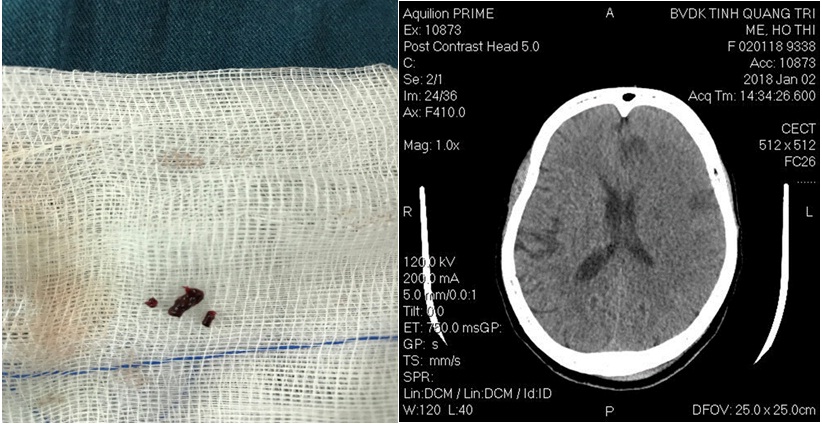

Hình: Các cục huyết khối được lấy ra và hình CLVT sọ não sau 2 ngày.

- Sau can thiệp B/N liệt cải thiện (cơ lực tay chân 3/5)